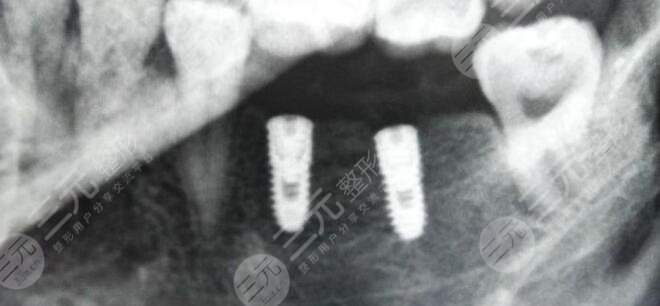

牙齒雖然說是人體很堅(jiān)固的部位之一,但如果在日常生活當(dāng)中不注重牙齒清潔和護(hù)理的話,也會(huì)導(dǎo)致牙齒出現(xiàn)各種各樣的問題,從而影響到一個(gè)人的咀嚼功能,因此就需要通過修復(fù)技術(shù)來進(jìn)行修復(fù)。牙齒種植是一種理想的牙齒修復(fù)方式,通過此項(xiàng)技術(shù)能夠很好的改良牙齒缺失問題,使牙齒外觀和咀嚼功能恢復(fù)到與真牙接近的狀態(tài),因此受到了很多愛美女性的信任和追捧。

而牙齒種植體也是大眾一直都很關(guān)注的熱點(diǎn),不同的種植體在價(jià)格、優(yōu)勢(shì)以及缺點(diǎn)方面都是存在一定不同的,下面就針對(duì)牙齒種植體十大排名來為大家進(jìn)行一個(gè)簡(jiǎn)單的盤點(diǎn),大家可以大概的了解一下,并從中選擇出自己理想的牙齒種植體材料。

一、牙齒種植體十大排名